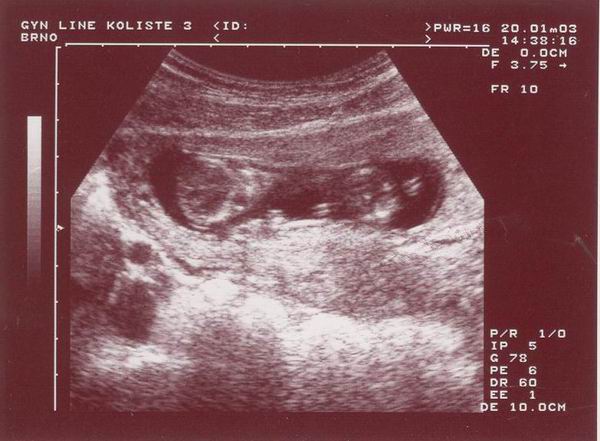

Takto jsem vypadal deset týdnů poté, co mě rodiče vymysleli.